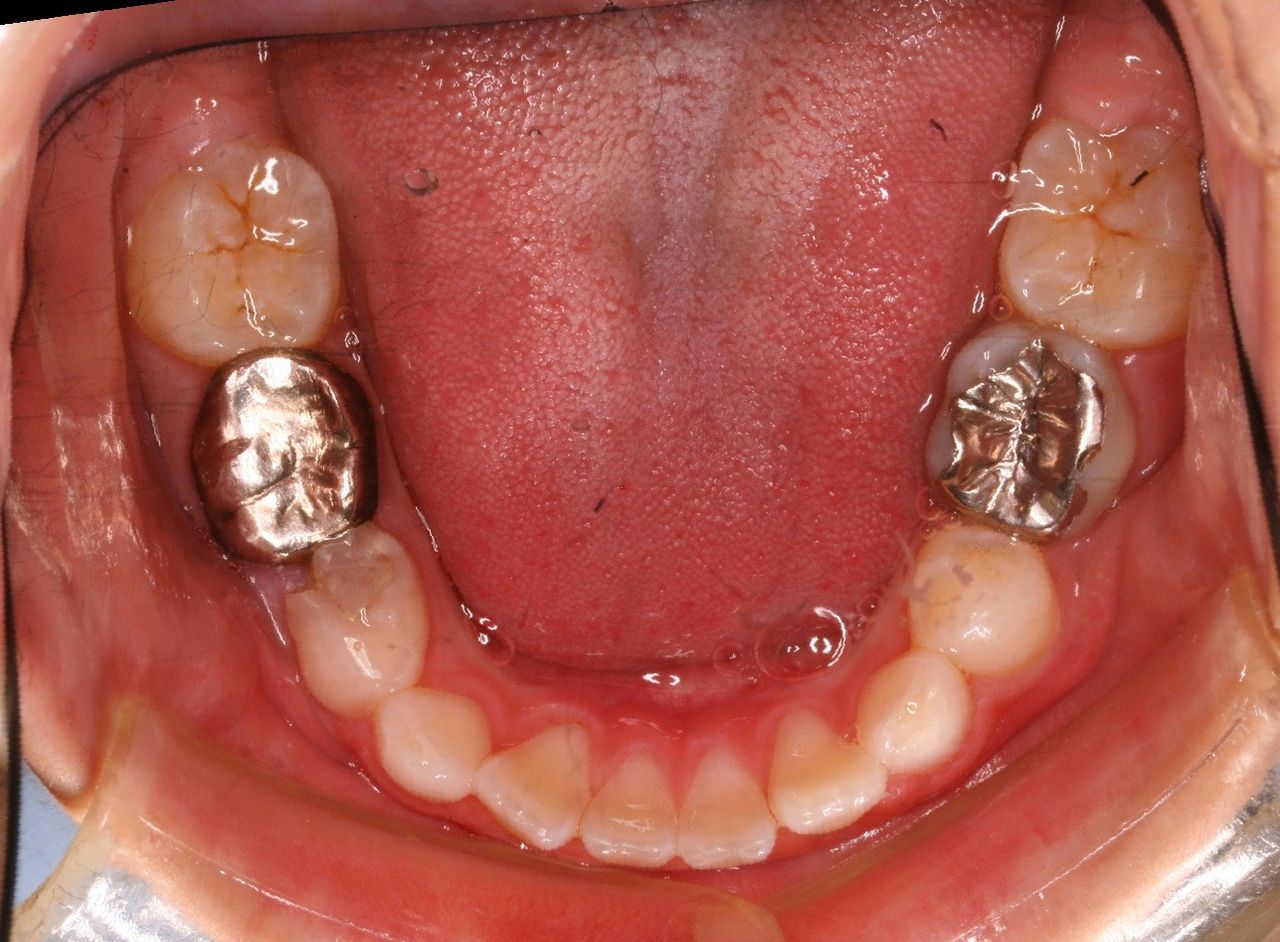

現在の状況です

中学2年生になりました。

上顎も下顎もそこそこの歯列になっていると思います。

咬み合わせも良好です

なんと、大人の歯は虫歯0本で管理されてます!

こういった部分は歯列矯正の技術的な部分はまったくなく、知識という部分をふんだんに応用した結果です。